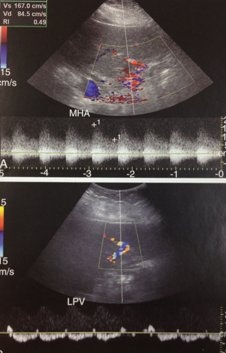

HV/IVC thrombosis

PV obstruction

cavernous transformation of PV